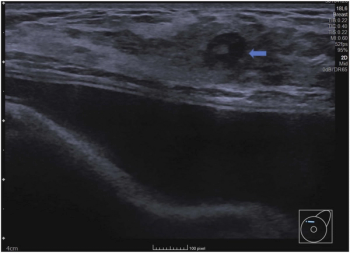

In a comparison of image-to-text large language models (LLMs), ChatGPT 4.0 offered a 95 percent sensitivity rate and an 83 percent AUC that were comparable to that of two senior radiologists and one junior radiologist interacting with LLM to differentiate between malignant and benign thyroid nodules on ultrasound.